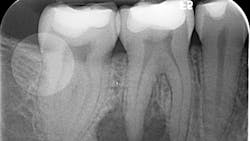

Various clinical presentations and risk factors can influence endodontic success or failure, including but not limited to the quality of the root canal performed and the seal of the coronal restoration.2 In addition to the aforementioned factors, the presence and size of a periapical lesion can directly affect the prognosis and treatment outcome. Classic literature highlights this shift in long-term success rates from 96% for vital/nonvital cases without the presence of a periapical lesion to 86% when a periapical lesion is present.3

Periapical radiographs have been commonly used to evaluate the size of periapical lesions. However, periapical radiographs have limitations, because the information is rendered in only two dimensions. A periapical lesion can only be detected in the radiograph when the mineral loss of bone reaches 30%–50%.4